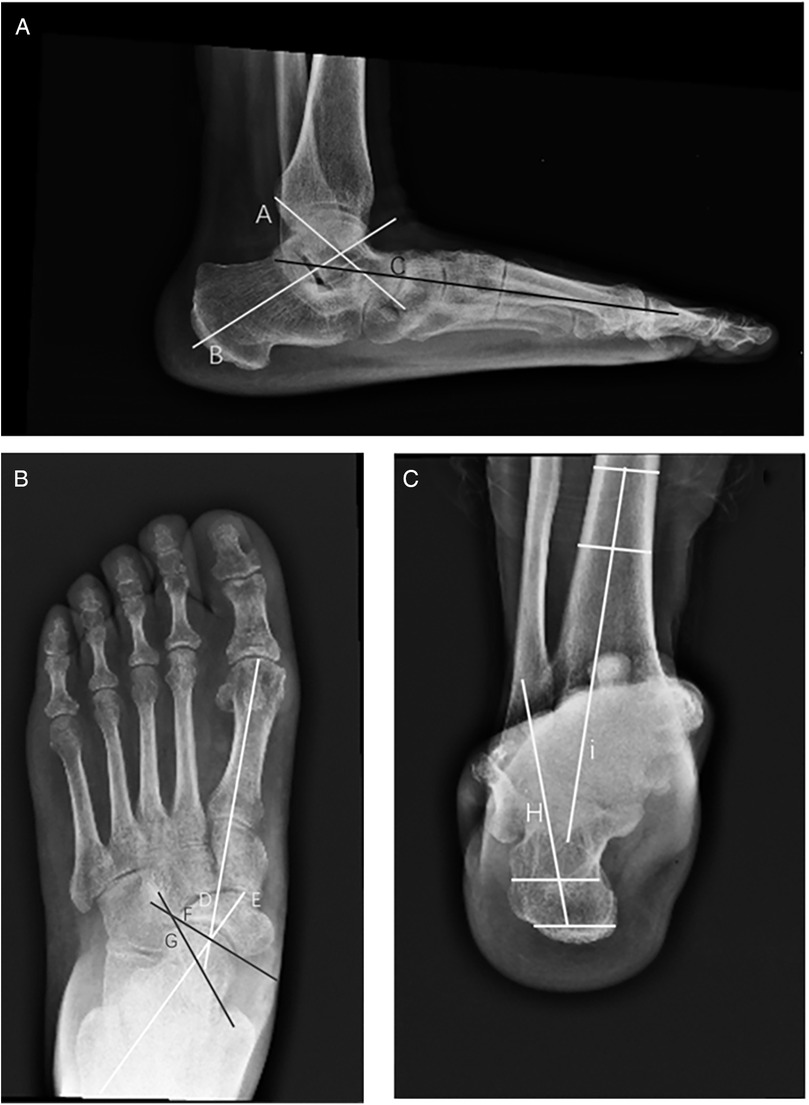

This retrospective cohort study was designed to analyze the outcomes of patients who underwent surgical intervention for AALTF with PCFD, with the goal of assessing the efficacy and clinical outcomes of different surgical strategies. The study was conducted between March 2014 and October 2024. A total of 70 patients (36 men and 34 women; mean age, 41.2 years; age range, 21–57 years) who had experienced persistent sinus tarsi pain for at least 3 months after failing non-operative treatment and were followed up for at least 2 years were included in the study. Sinus tarsi pain was confirmed during physical examination at the outpatient clinic by the presence of recognizable tenderness on palpation right at the sinus tarsi. Preoperative plain radiographs and magnetic resonance imaging (MRI) images were also collected for all candidates, with MRI used to confirm the presence of AALTF. AALTF is defined as a small joint that extends continuously from the posterior talar process to the lateral talar process on sagittal T1-weighted images (4) (Figure 1). All 70 patients included in the study met this radiographic criterion for AALTF.

Figure 1. AALTF is anatomically identified as a bony protuberance arising from the lateral talar process and extending anteriorly to articulate with the calcaneus. (A) It is typically observed on sagittal T1-weighted MRI as a discrete osseous structure that contributes to talocalcaneal impingement in patients with flatfoot deformities (arrow). (B) Sagittal MRI (T2) imaging proving the presence of an osseous protuberance and the bone marrow edema located at the opposing calcaneal side of the AALTF (circle).